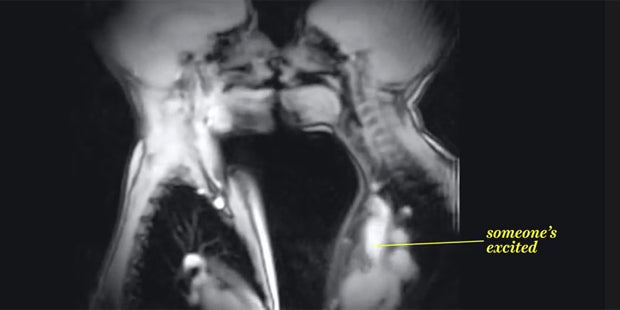

MRT-Aufnahmen von Sex, Zungenkuss und Geburt erobern das Internet.

So schlüpfrig kann Wissenschaft sein: Diese Aufnahmen eines MRT-Scanners gewähren tiefe Einblicke. Das Video von "Vox.com" hat sich innerhalb weniger Tagen auf Youtube rasant verbreitet. Es zeigt verschiedene Vorgänge innerhalb des menschlichen Körpers, wie etwa Essen und Trinken oder die Geburt. Der Clip enthält aber auch Zwischenmenschliches, wie Zungenküsse und Sex.

Bei einer MRT werden Schnittbilder des Körpers angefertigt. Sie basiert auf dem Prinzip, dass durch ein sehr starkes Magnetfeld bestimmte Atomkerne angeregt werden und anschließend deren Ordnung durch Radiowellen gestört wird. Diese Atomkerne - vorwiegend Wasserstoffatome - strahlen dann ein extrem schwaches elektromagnetisches Feld aus, welches das MRT-Gerät empfängt und in ein Bild übersetzt.